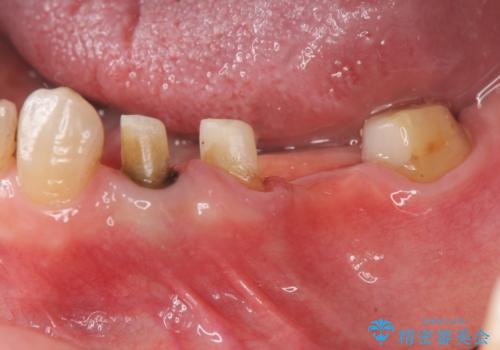

- 古くなり黒ずんできたブリッジのやりかえを希望され来院されました。

老朽化した銀パラジウム合金のブリッジを除去し、ジルコニア製のブリッジでやりかえを計画します。